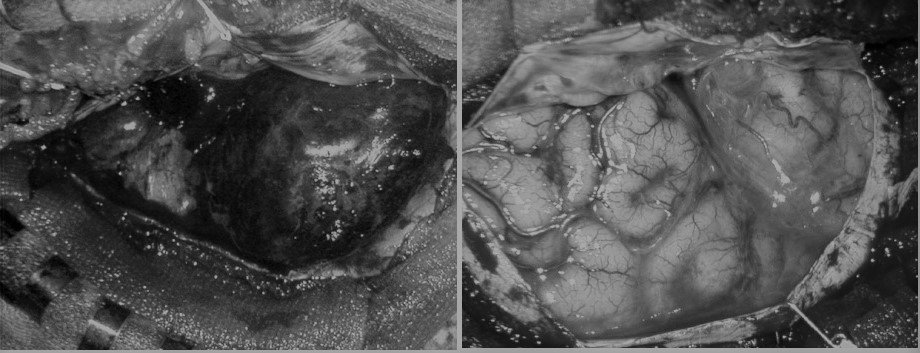

図:くも膜下出血を起こした脳(左)と正常の脳(右)手術中所見より

(画像にカーソルを合わせると、カラーに変わります)